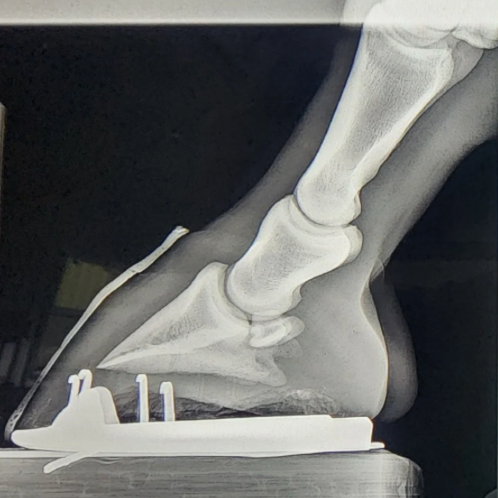

Fractura Tejuelo o P3

Realizamos tratamientos especializados para fracturas en P3 (hueso tejuelo), comunes en potros y foals debido a traumatismos o caídas durante sus primeros meses.

Ángulo Palmar Negativo

El ángulo palmar negativo es una alteración en la orientación del hueso del pie, debida a una falta de tensión en el tendón digital profundo. Esto se traduce en ranillas prolapsadas, talones colapsados y problemas funcionales que comprometen el bienestar y el rendimiento del caballo. A través de un herraje especializado trabajamos para restablecer el equilibrio del casco y su correcta biomecánica.